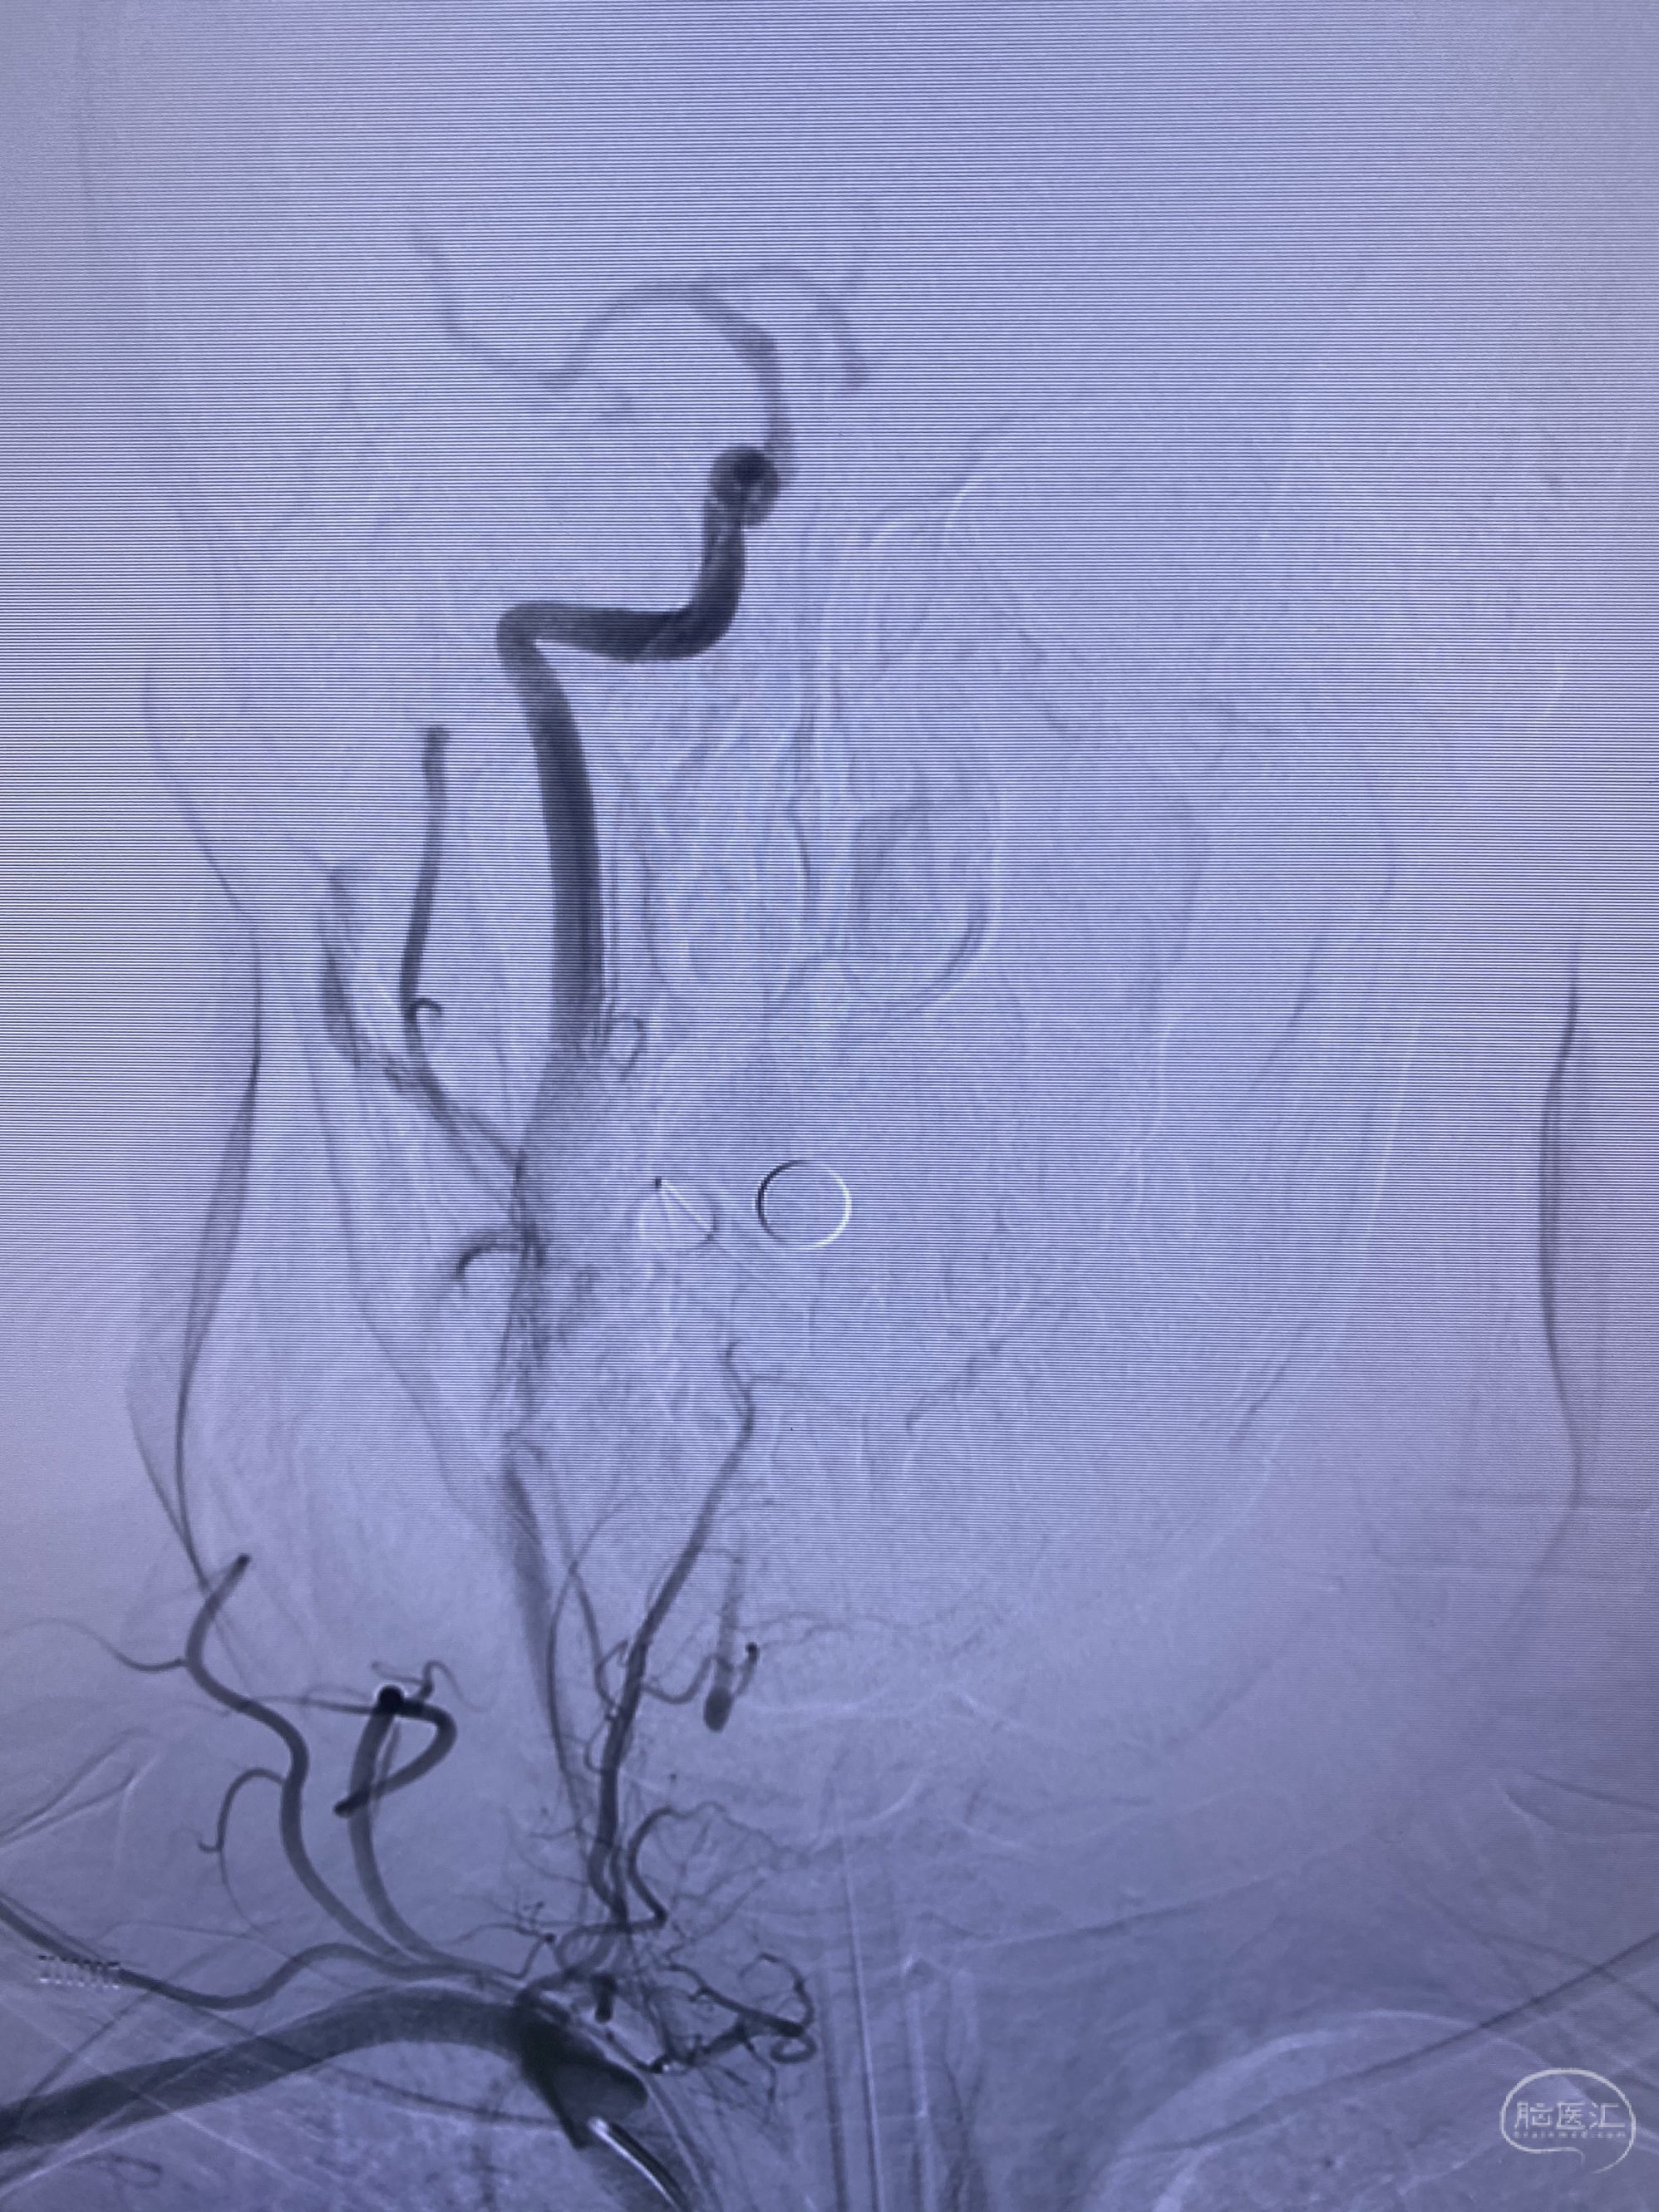

今日手术,TJG,M62Y,一期左侧颈动脉狭窄支架植入,二期椎动脉V4段多发夹层动脉瘤伴狭窄,常规支架辅助栓塞方法复杂又危险,血流导向装置植入快捷又安全。南阳市中心医院神经内科脑血管病介入团队pipeline flexFD植入两人导师资格。

椎动脉颅内段多发夹层动脉瘤伴载瘤动脉狭窄pipeline flex植入

今日手术,TJG,M62Y,一期左侧颈动脉狭窄支架植入,二期椎动脉V4段多发夹层动脉瘤伴狭窄,常规支架辅助栓塞方法复杂又危险,血流导向装置植入快捷又安全。南阳市中心医院神经内科脑血管病介入团队pipeline flexFD植入两人导师资格。